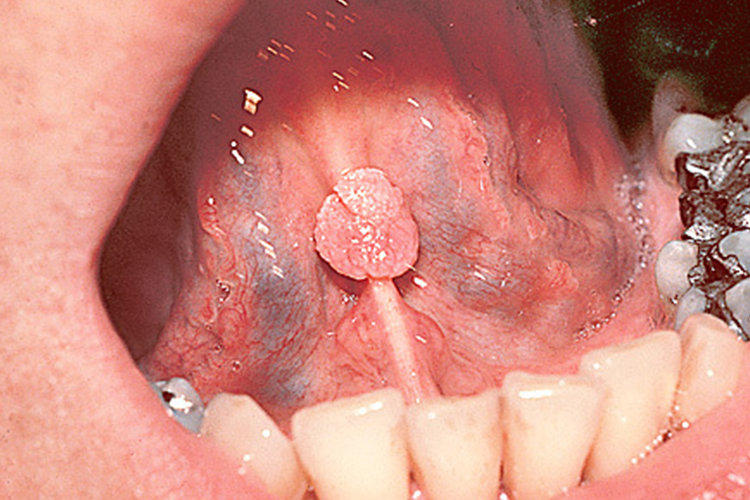

女性口腔尖锐湿疣表现为咽喉处、舌系带下、舌根或舌尖等口腔部位出现多个赘生物,可为扁平状、乳头状、鸡冠状或菜花状。

女性口腔尖锐湿疣可出现在咽喉处、舌系带下、舌根或舌尖等部位。初起时,为小而柔软,淡红色顶端稍尖的丘疹,逐渐增大增多,互相融合形成各种不同的形态,表面不平,湿润柔软呈乳头状、菜花状及鸡冠状。根部可有蒂或无蒂,带蒂者基部稍宽。疣体表面呈白色,暗灰色或红色,易出血。舌根部位尖锐湿疣会产生吞咽不适感。咽喉处尖锐湿疣可造成声嘶及呼吸困难等症状。